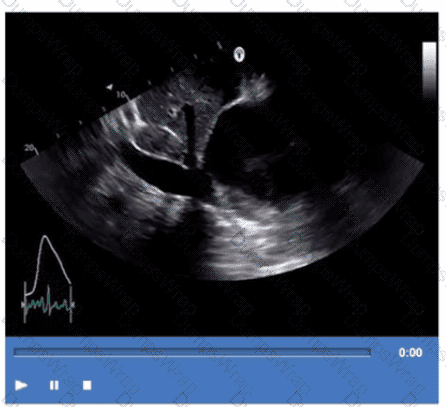

Which finding is demonstrated in this video?

Options:

Bioprosthetic valve replacement

Mechanical valve replacement

Annuloplasty ring repair

Native valve with extensive calcification

Answer:

CExplanation:

The echocardiographic video shows a prosthetic ring-like structure attached to the mitral annulus with preserved native leaflet motion, consistent with an annuloplasty ring repair. Annuloplasty rings are used to reduce the mitral annulus size and improve leaflet coaptation in mitral regurgitation without replacing the valve.

Bioprosthetic or mechanical valve replacements would show distinctly different echogenic valve structures with leaflet or disc motion replacing the native valve. Extensive calcification of a native valve appears as echogenic, thickened leaflets without a discrete ring.

This is described in the "Textbook of Clinical Echocardiography, 6e", Chapter on Mitral Valve Repair Techniques【20:400-405†Textbook of Clinical Echocardiography】.